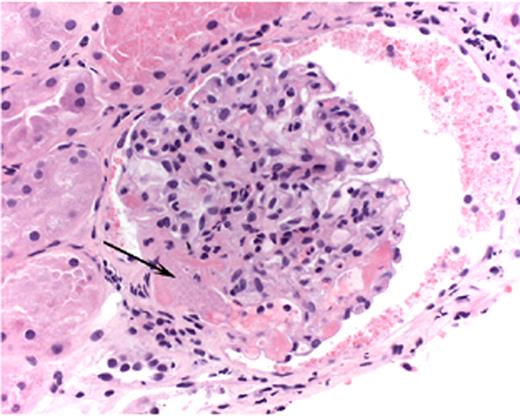

Hambleton Figure 5. Light micrograph of a glomerulus with fibrin-platelet thrombus in afferent arteriole (arrow) as it enters the glomerulus.

Note red blood cell fragments within thrombus (H&E).

Courtesy of Dr. Jean Olson, Department of Pathology, University of California, San Francisco.